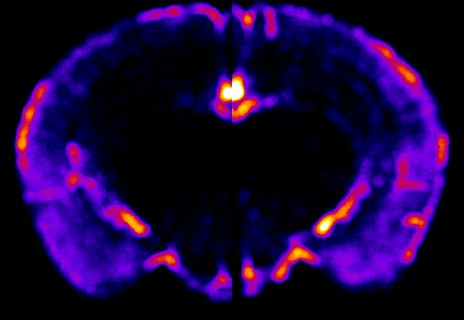

The mechanisms by which the auditory cortices develop unique sound processing capabilities remain unknown. Recent research conducted in our lab has indicated notable variations in the maturation trajectory of the auditory cortices. To gain insights into the molecular pathways responsible for these differences, we investigate changes in gene expression between the auditory cortices using spatial transcriptomics.